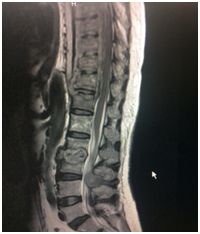

MRI Lumbo sacral Spine showed altered signal intensity involving L2-L3 vertebral endplates and intervertebral disc with enhancing pre and paraspinal soft tissue component. Extension noted into the posterior elements of L3 vertebral body with posterior epidural component. No significant canal stenosis noted at this level.

MRI Dorsal spine shows -Contiguous altered vertebral body signal intensity also imaged at D4 to D12 levels with enhancing pre and paraspinal soft tissue component. Epidural component noted at this level with e/o cord compression and cord signal changes, Disease shows progression when compared to MRI on 4/6/16 (Figure 2). Stain, AFB Stain, TB-PCR, Culture and sensitivity (bacterial, fungal, anaerobic culture).

Figure 2 MRI was 27/08/2017.